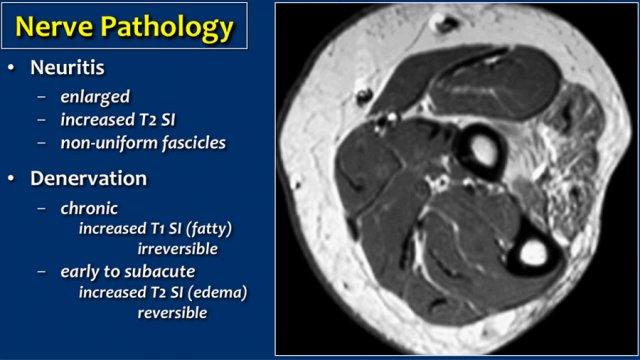

Denervation

Bệnh lý thần kinh có thể biểu hiện dưới dạng dày lên của dây thần kinh khi có viêm thần kinh hoặc do chèn ép dây thần kinh.

Dấu hiệu thứ phát của bệnh lý thần kinh là mất phân bố thần kinh với phù nề và/hoặc teo cơ.

Trong trường hợp này có teo mãn tính với tín hiệu cao trên T1, đây là tình trạng không hồi phục.

Trong giai đoạn mất thần kinh chi phối sớm hoặc bán cấp, dấu hiệu nổi bật là phù nề với tín hiệu cao trên ảnh T2W và có thể hồi phục.